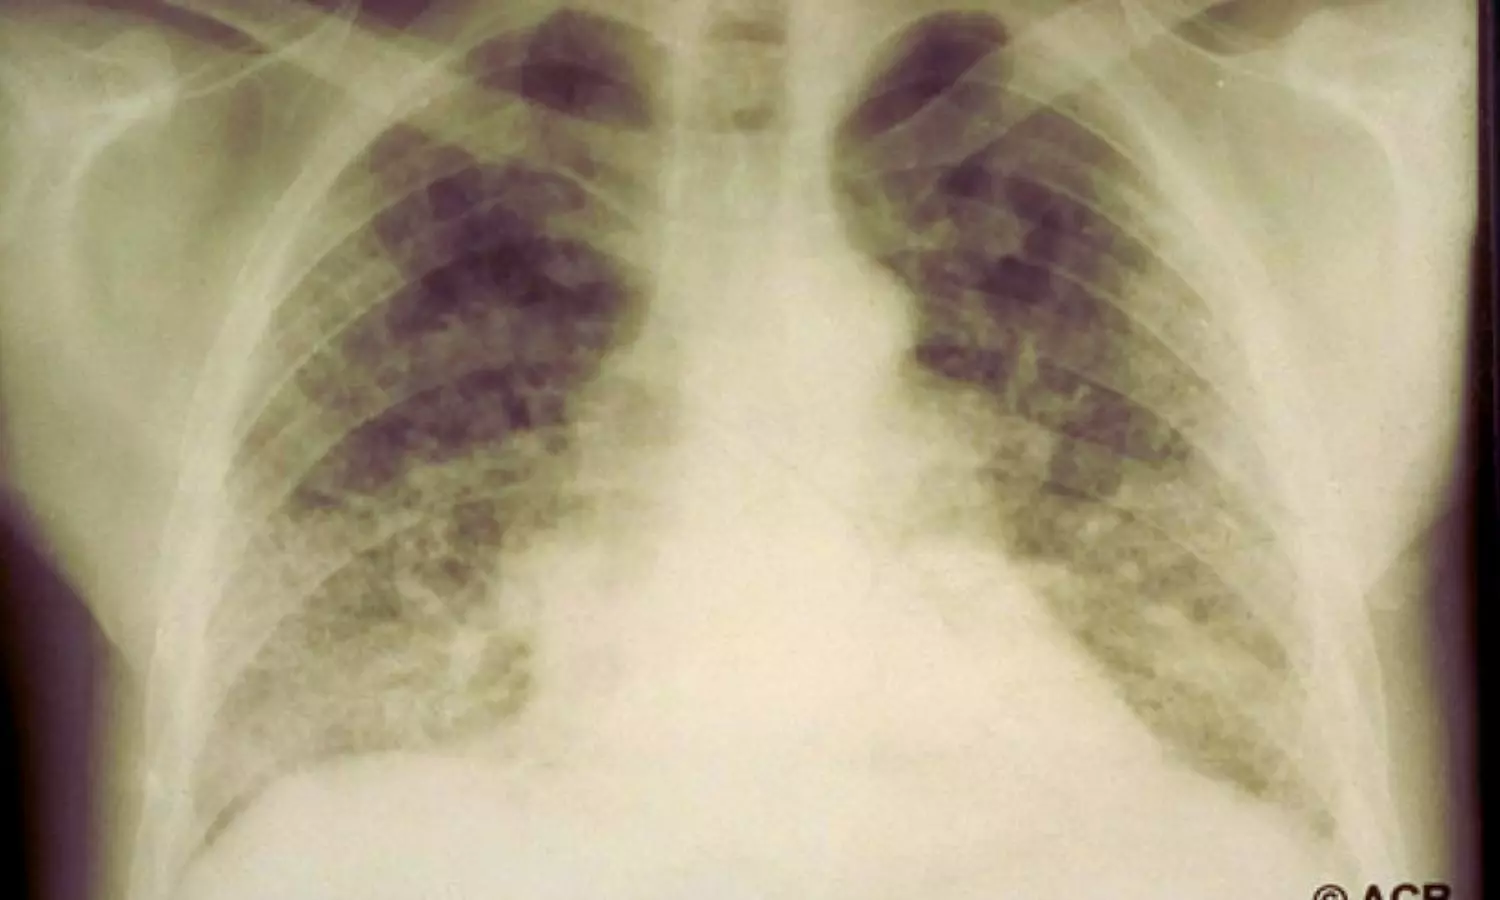

The study assessed mortality risks among patients with RA-associated interstitial lung disease (RA-ILD) or bronchiectasis (RA-BR), collectively termed RA-associated lung disease (RA-LD), compared to those with RA but no lung involvement (RA-no LD). Using retrospective data from the Mass General Brigham Biobank, the researchers analyzed 221 individuals with RA-LD and 980 matched comparators without lung disease, considering variables like age, sex, RA duration, and time of diagnosis.

- Respiratory-related deaths were significantly more common in RA-LD patients, particularly in those with RA-ILD.

- The risk of respiratory mortality in RA-ILD patients was nearly seven times higher (sdHR 6.68) than in RA-no LD patients.

- Mortality due to lung infections in RA-LD patients was over three times higher (sdHR 3.33) than in the comparator group.